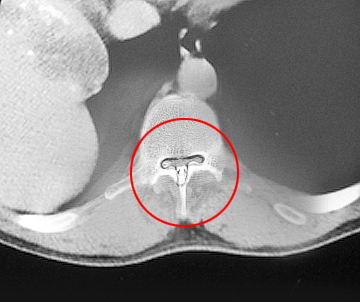

Spine X-rays are radiological tests carried out to rule out other causes such as a tumor or infection. Sometimes, a CT scan or MRI is ordered to get a more detailed examination of the bone or soft tissues. Rarely, Myelography is performed which involves injection of a contrast material into the spine followed by X-rays to detect any pathology of the spine. These tests help in the diagnosis and treatment plan.